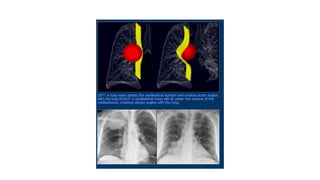

Diagrammatic explanation for the meniscus sign

CT chest

Homogenous , high

Attenuation

Meniscoid

0-20 HU